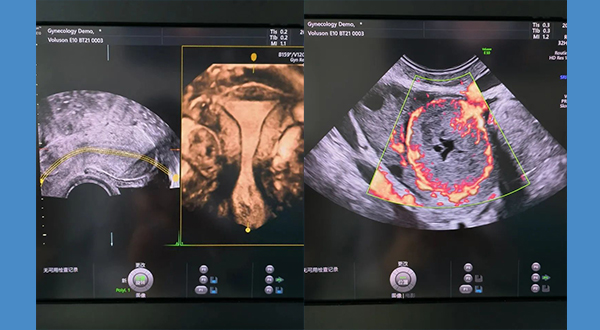

陰道超聲安全嗎?

1.什么是陰道超聲?婦科超聲檢查一般包括經(jīng)腹超聲和經(jīng)陰道超聲。經(jīng)腹超聲是將超聲探頭放在下腹部觀察子宮及附件的情況,在檢查前半小時(shí)至1小時(shí)需要飲水1000ml左右,使膀胱充盈才能獲得滿意的超聲圖像,如果患者肥胖,脂肪較厚,腸道糞便未清理 閱讀量:4031